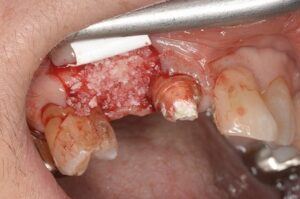

このままではインプラントができませんので骨に変わる材料を補填していきます